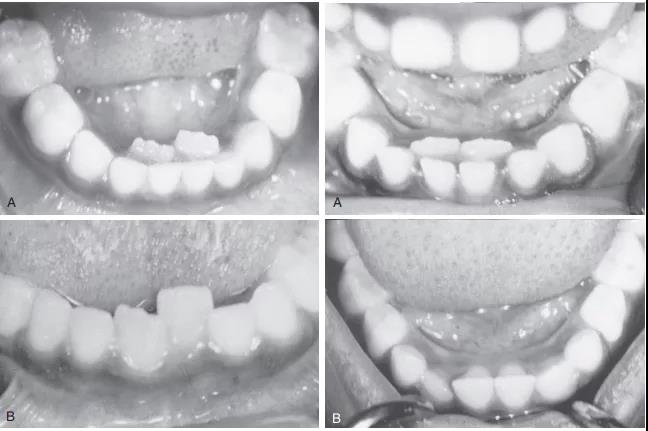

还没等乳牙“下岗”,恒牙就迫不及待地“上岗”了,于是就成了“双排牙”,一张嘴就好像“小怪兽”!

“双排牙”的出现就是当儿童的恒牙已经萌出时,而对应的乳牙却并未脱落,从而形成两排牙齿,出现的这种现象,就叫做乳牙滞留,俗称“双排牙”。

由于正常的生长空间不足,恒牙会顶着大于一个乳牙甚至两个乳牙的阻力,从旁边阻力较小的地方生长出来,导致两颗牙在并排“工作”,就形成了双排牙。

实际上,很多研究显示在舌头和嘴唇的塑形作用下,95%的恒牙可能回归原位。

但是是否整齐就要看原来的乳牙有没有给他们留足够的空间了(即便空间不够恒牙也会向小空隙中移动,但是会扭转错位)。